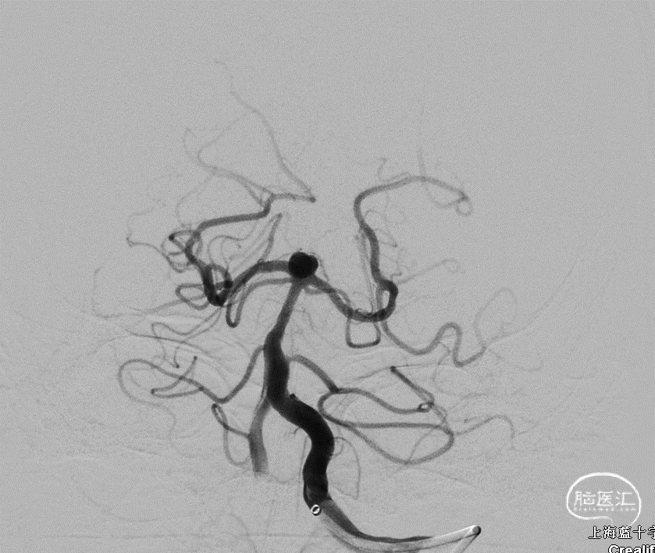

左侧椎动脉正侧位造影,可见基底动脉尖动脉瘤

3D DSA评估动脉瘤体和载瘤动脉形态:动脉瘤呈现“甜瓜”状,侧位显示瘤底指向前方,瘤颈处靠后方还有一小泡,形态不规则。

术后正侧位造影,动脉瘤2级栓塞

术后即刻 Raymond II